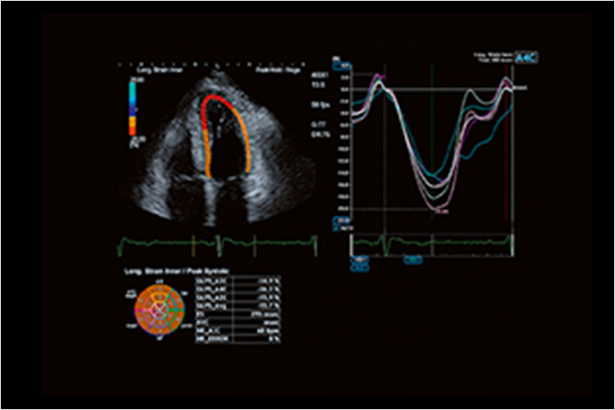

Aplio高級室壁運動追蹤技術能夠以2D的形式,即時顯示并定量心肌整體及節段室壁運動的動態變化